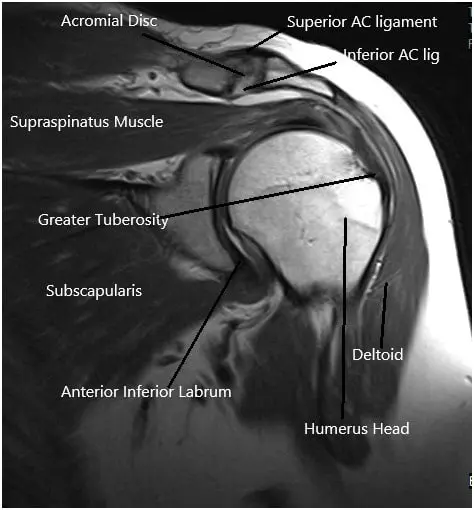

MRI of the shoulder joint.

- Imaging: X-rays are used to identify structural issues like fractures or arthritis, while MRIs or CT scans help visualize soft tissue damage, such as rotator cuff tears or labral injuries.

The shoulder joint consists of the humerus (upper arm bone), scapula (shoulder blade), and clavicle (collarbone). The ball of the humerus fits into the shallow socket of the scapula, forming a ball-and-socket joint. This configuration provides a large range of motion. Ligaments, tendons (like the rotator cuff), and the labrum stabilize and support the joint, allowing for smooth movement and flexibility.